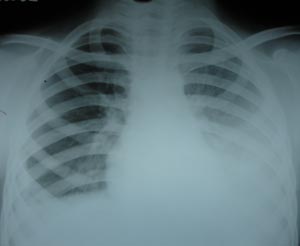

View Pleural effusion

Pleural effusion